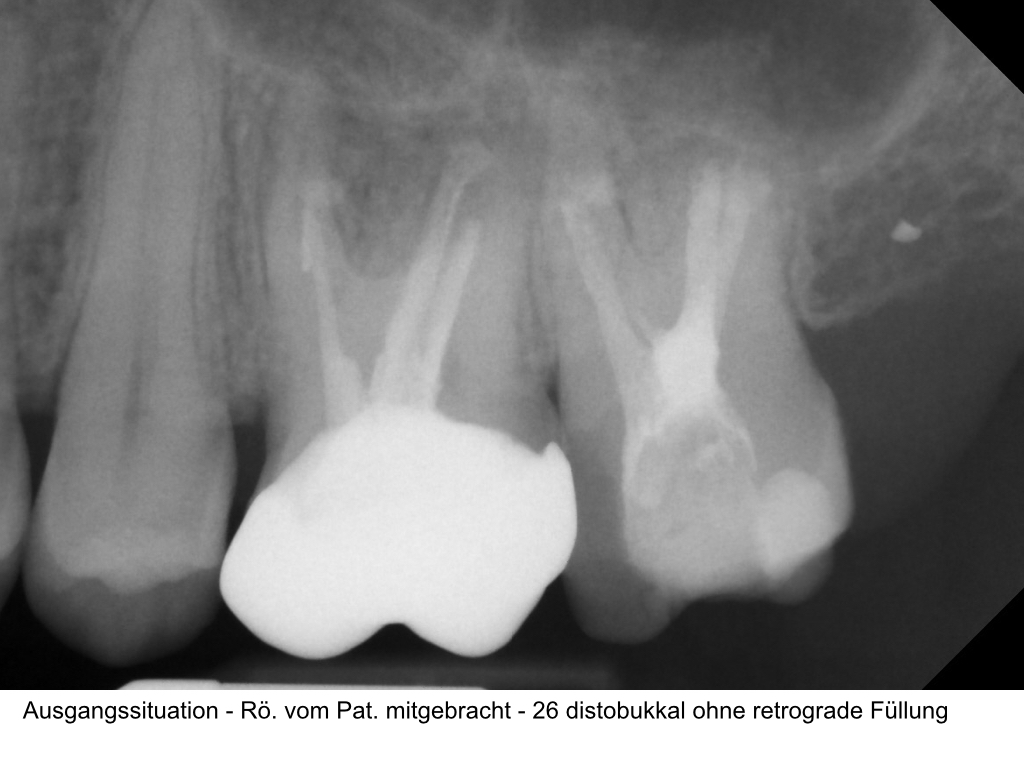

WS15_10.001

1024 × 768

Zustand nach WSR